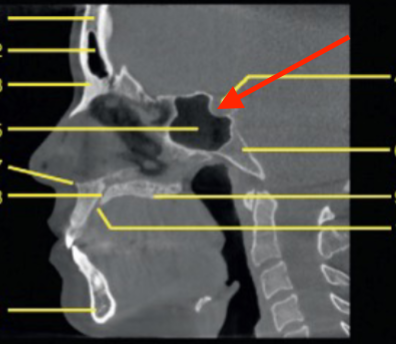

nasopharynx

identify the region indicated

oropharynx

identify 5

soft palate

identify the structure

tongue

epiglottis

C1